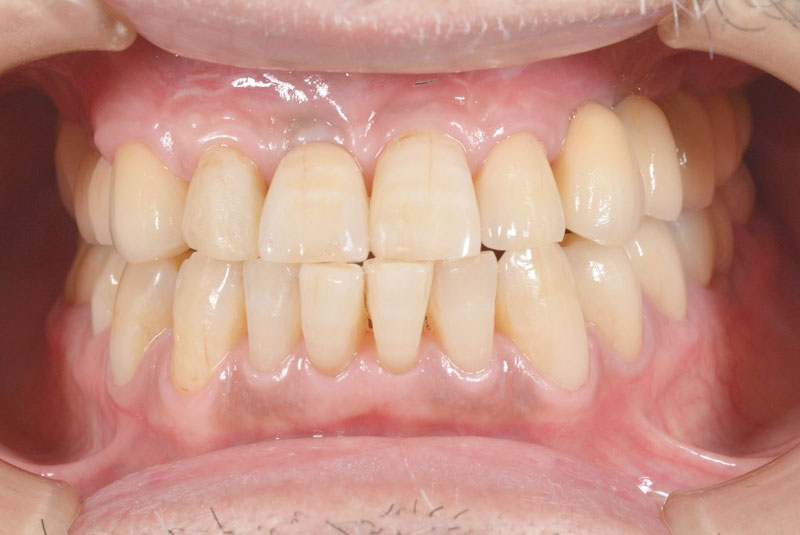

前歯のインプラント

-

術前

術後

- 患者

- 30代女性

- 主訴

- 他院で治療中の歯が折れて無くなった。

前医で前歯の治療を数か月していたが抜歯を勧められた。悩んでいたところ歯が折れてしまった。

- 治療経過

- 両側の歯を削りたくないのでインプラント治療を希望された患者さんです。前歯部インプラントの難易度はずばり審美性です。前歯なのでできる限り隣の歯と合わせる必要があります。特に1本欠損で両側が天然歯というのは難易度の高い症例です。この患者さんは決断が早く、歯槽骨まで感染が及んでいなかったため抜歯と同時のインプラント埋入を行うことで骨移植等を行うことなく治療可能でした。前歯は場合によっては審美性を確保するために歯肉移植が必要なことも多く、当院では歯肉移植を行うかどうかは患者さんと相談させていただいております。